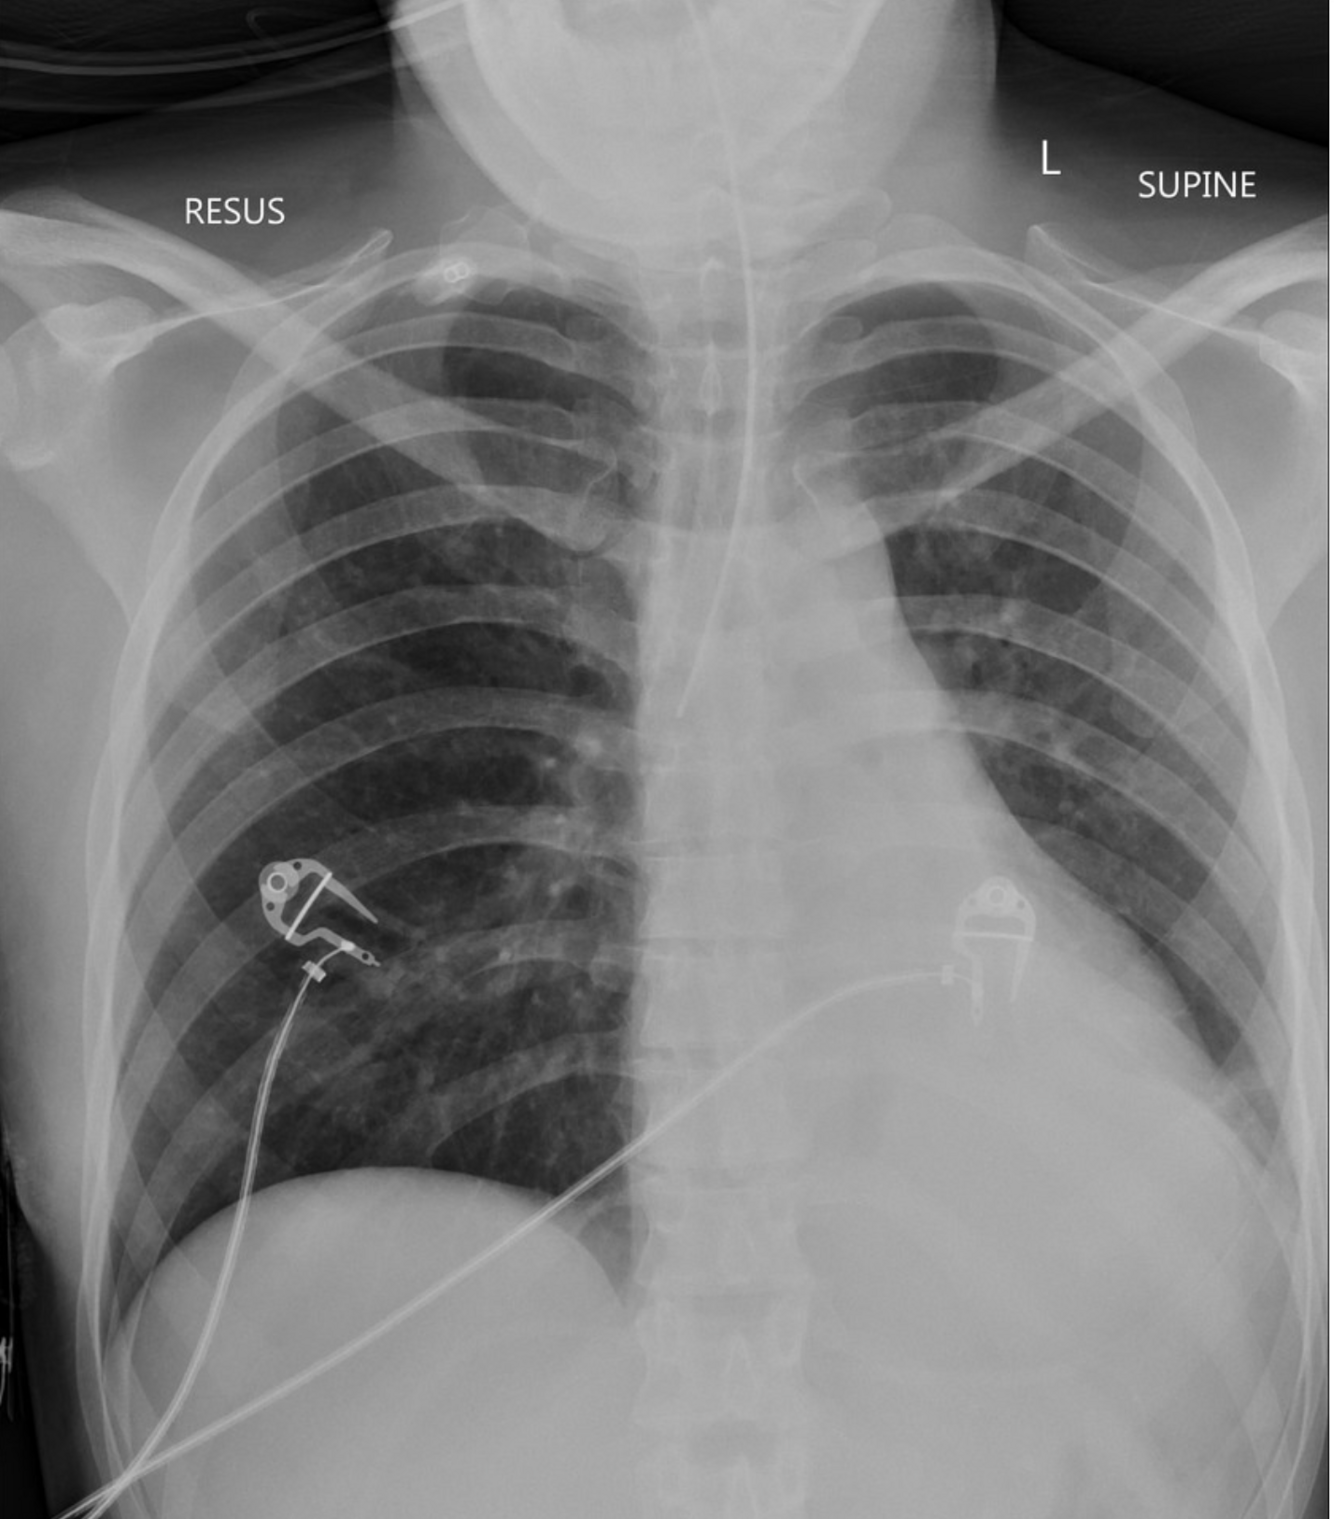

A 30-year-old woman is brought to a rural emergency department by paramedics due to tonic-clonic seizure activity.

The patient is administered multiple doses of lorazepam and levetiracetam over the course of 10 minutes, which fail to terminate the seizure. A decision is made to perform rapid sequence intubation and initiate intravenous propofol. A post-intubation chest x-ray is obtained and shown below. The hospital does not have an on-call radiologist so the image is sent to a teleradiology service for formal interpretation. Which of the following is the next best step in the management of this patient?

This patient undergoes endotracheal intubation. A chest x-ray is subsequently obtained, revealing that the endotracheal tube tip is located in the right mainstem bronchus. This patient’s chest x-ray demonstrates right mainstem intubation, which can lead to hypoxemia, barotrauma of the right lung, and atelectasis of the left lung. In contrast, the tip of a properly positioned tube should terminate approximately 3-5 cm above the carina to ensure that both lungs are ventilated. The endotracheal tube should be immediately retracted to ensure both lungs are ventilated. It would be inappropriate to wait for the final report from teleradiology before intervening. As such, this tube should be retracted.

It is important for clinicians to be able to personally interpret chest x-rays, as a radiologist may not always be available. When reviewing chest x-rays, it is important to follow a systematic approach to minimize the risk of overlooking pathological findings.